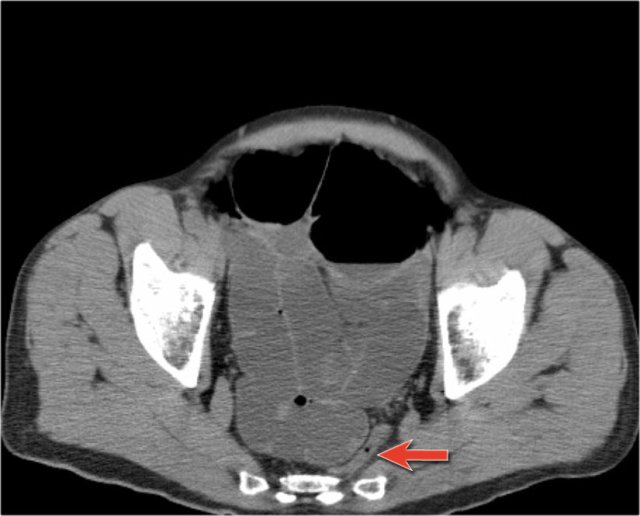

On the left we see images of a patient in whom obstruction was not suspected.

This patient also received positive oral contrast.

Look for the major findings and then continue.

First you will notice that the small bowel is not dilated.

When you go down to the pelvis you see a dilated loop of bowel with inhomogeneous content and finally deep down in the pelvis there is a C-shaped dilated bowel indicating a closed loop obstruction.

The other important finding in this patient is the 'Small Bowel Feces Sign' (SBFS: arrow).

The SBFS is a very useful sign as it is seen at the zone of transition from normal to obstructed bowel and thus facilitating identification of the point and the cause of the bowel obstruction.

The SBFS has been defined as gas and solid material within a dilated small-bowel loop that simulates the appearance of feces.